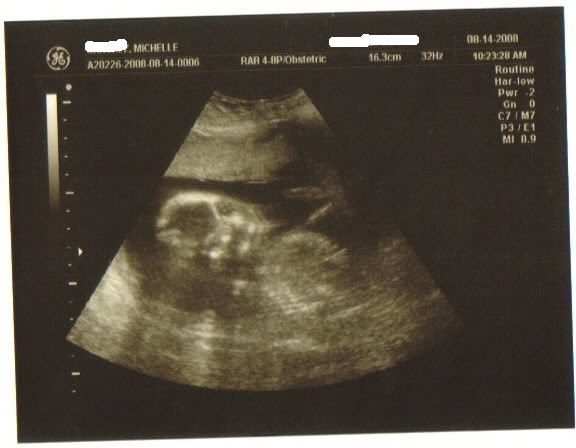

Here he is